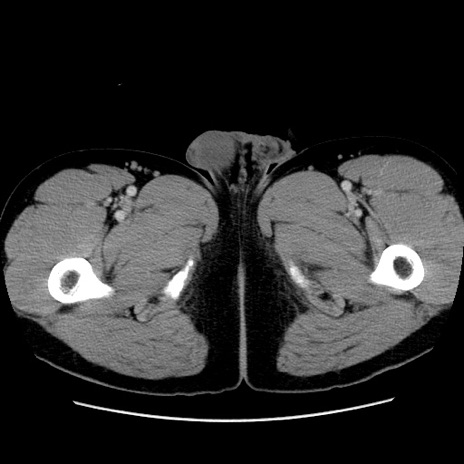

冠状断像

【症例】30歳代男性

【主訴】腹痛、嘔吐

【現病歴】昨晩から突然の腹痛あり、その後嘔吐、軟便も出現。腹痛が改善しないため救急搬送となる。2日前にしめ鯖の食事歴あり。

【身体所見】意識清明、苦悶様、BP 135/90mmHg、BT 35.7℃、腹部:平坦、やや硬、心窩部〜臍部に自発痛、圧痛あり、筋性防御+、反跳痛-

【データ】WBC 8100、CRP 0.57